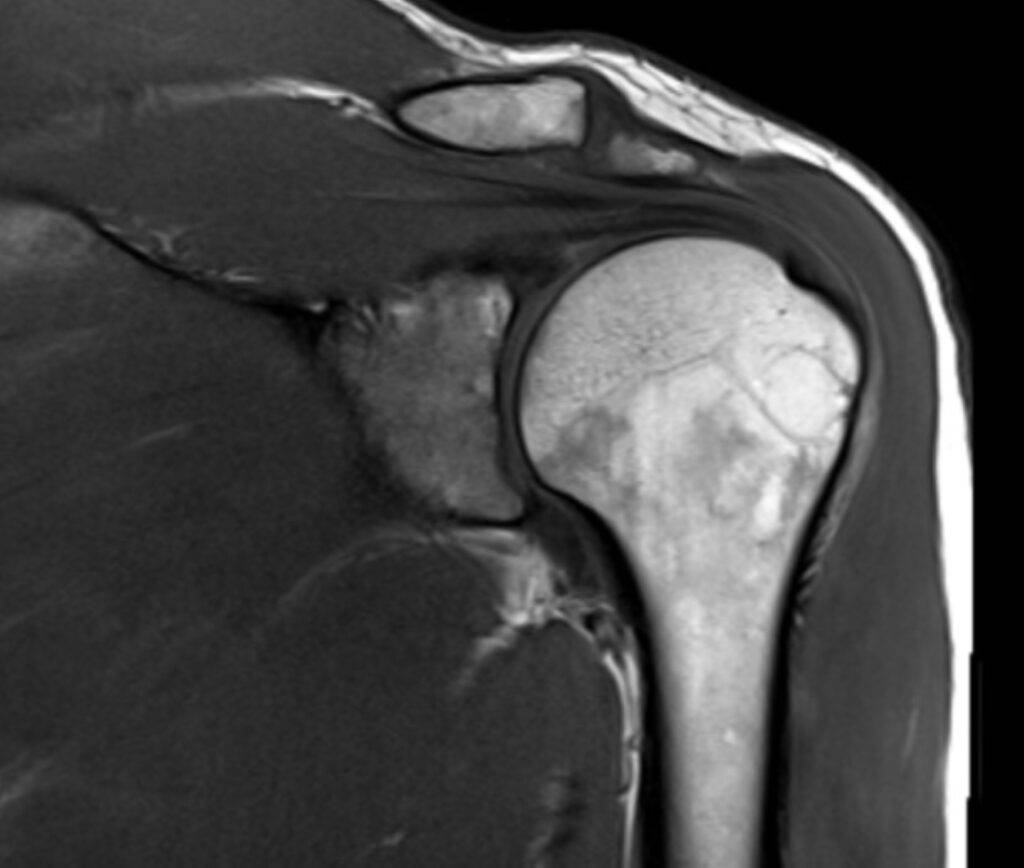

Die Magnetresonanztomographie der Schulter, kurz MRT Schulter genannt, ist eine bildgebende Untersuchung, die detaillierte MRT Bilder der Schulterstrukturen liefert, ohne Röntgenstrahlen zu verwenden. Sie ermöglicht die präzise Diagnose von Schulterschmerzen, Verletzungen, Arthrose und weiteren Erkrankungen der Schulter.

Eine Magnetresonanztomographie (MRT) oder auch Kernspintomographie der Schulter ist eine schmerzlose bildgebende Untersuchung, die ermöglicht die Strukturen im Schulterbereich präzise darzustellen. Es handelt sich hierbei um Querschnittbilder, die mithilfe von Magnetfeldern und Radiowellen ohne den Einsatz von ionisierender Strahlung erstellt werden. Mit der MRT können Knochen, Weichteile wie Muskeln und Sehnen, Gelenke sowie Nerven und Blutgefäße in der Schulterregion abgebildet werden. Dies ermöglicht die Diagnose von Schulterschmerzen, Verletzungen, Arthrose, Entzündungen und anderen Erkrankungen.

Was sieht man bei einer MRT Schulter?

| Gelenke und Knochen | Frakturen, Arthritis, weitere Gelenk-/Knochenprobleme |

| Bänder und Sehnen | Verletzungen oder Entzündungen |

| Schleimbeutel | Entzündung oder Schwellung |

| Rotatorenmanschette | Verletzungen oder Risse |

| Labrum | Verletzungen oder Risse |

| Nerven und Blutgefäße | Nervenkompression oder Gefäßveränderungen |